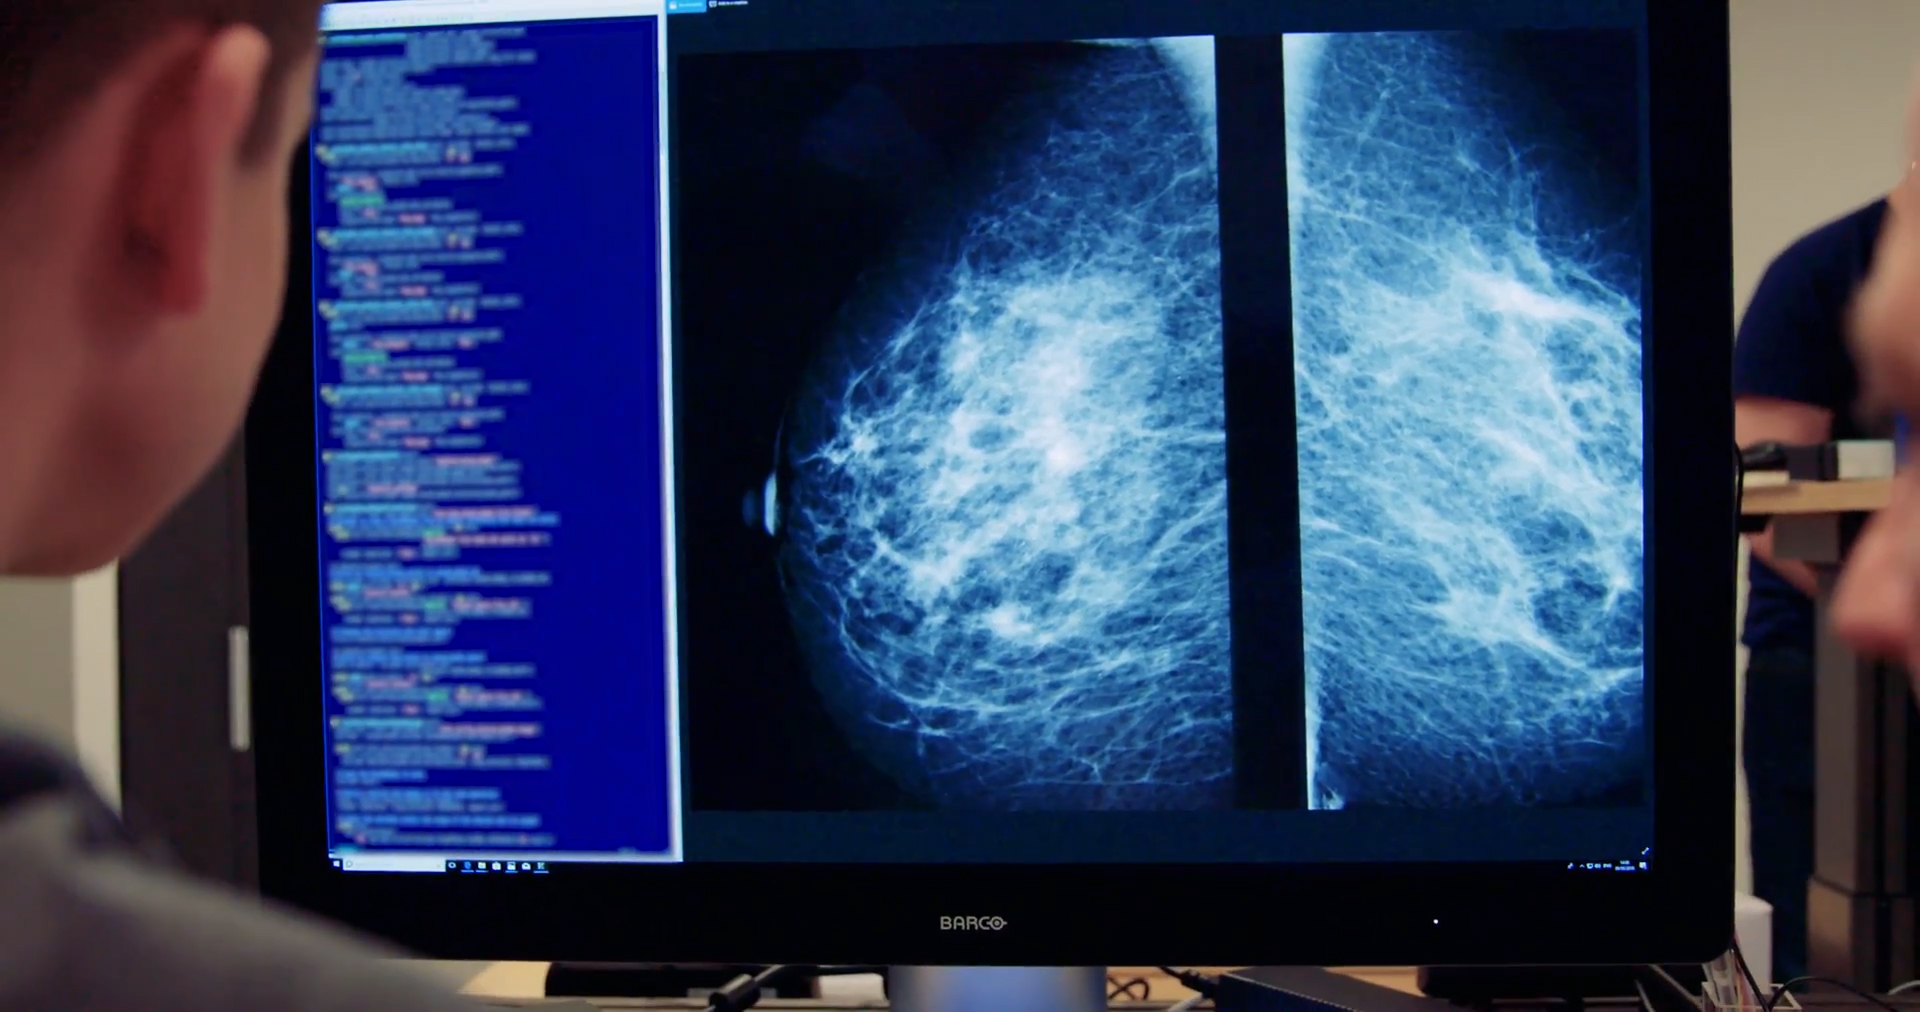

Программа, получившая название Mia, была опробована совместно с врачами NHS и проанализировала маммограммы более 10 000 женщин. Большинство из них не болели раком, но программа успешно выявила всех тех, у кого были симптомы, а также еще 11 женщин, заболевание у которых не выявили врачи.

Ни один из случаев, участвовавших в исследовании, не был проанализирован только Mia — каждый из них также рассматривался человеком. В настоящее время каждый отдельный снимок рассматривают два рентгенолога, но есть надежда, что в один прекрасный день один из них может быть заменен инструментом, что позволит вдвое снизить нагрузку на каждого из них.